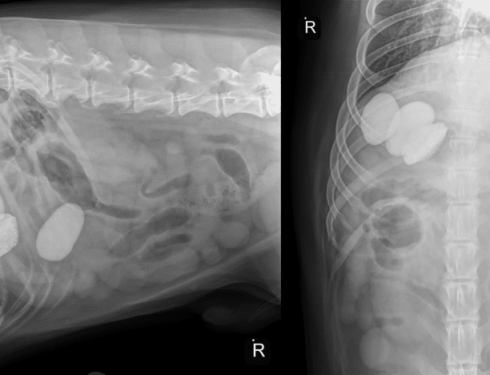

A Cat’s Close Call in a Dryer: The Real Risks of Laundry Machines for Pets

I was wasting time, mindlessly watching cat videos on Facebook, when I ran across this horrifying video. At first glance,…